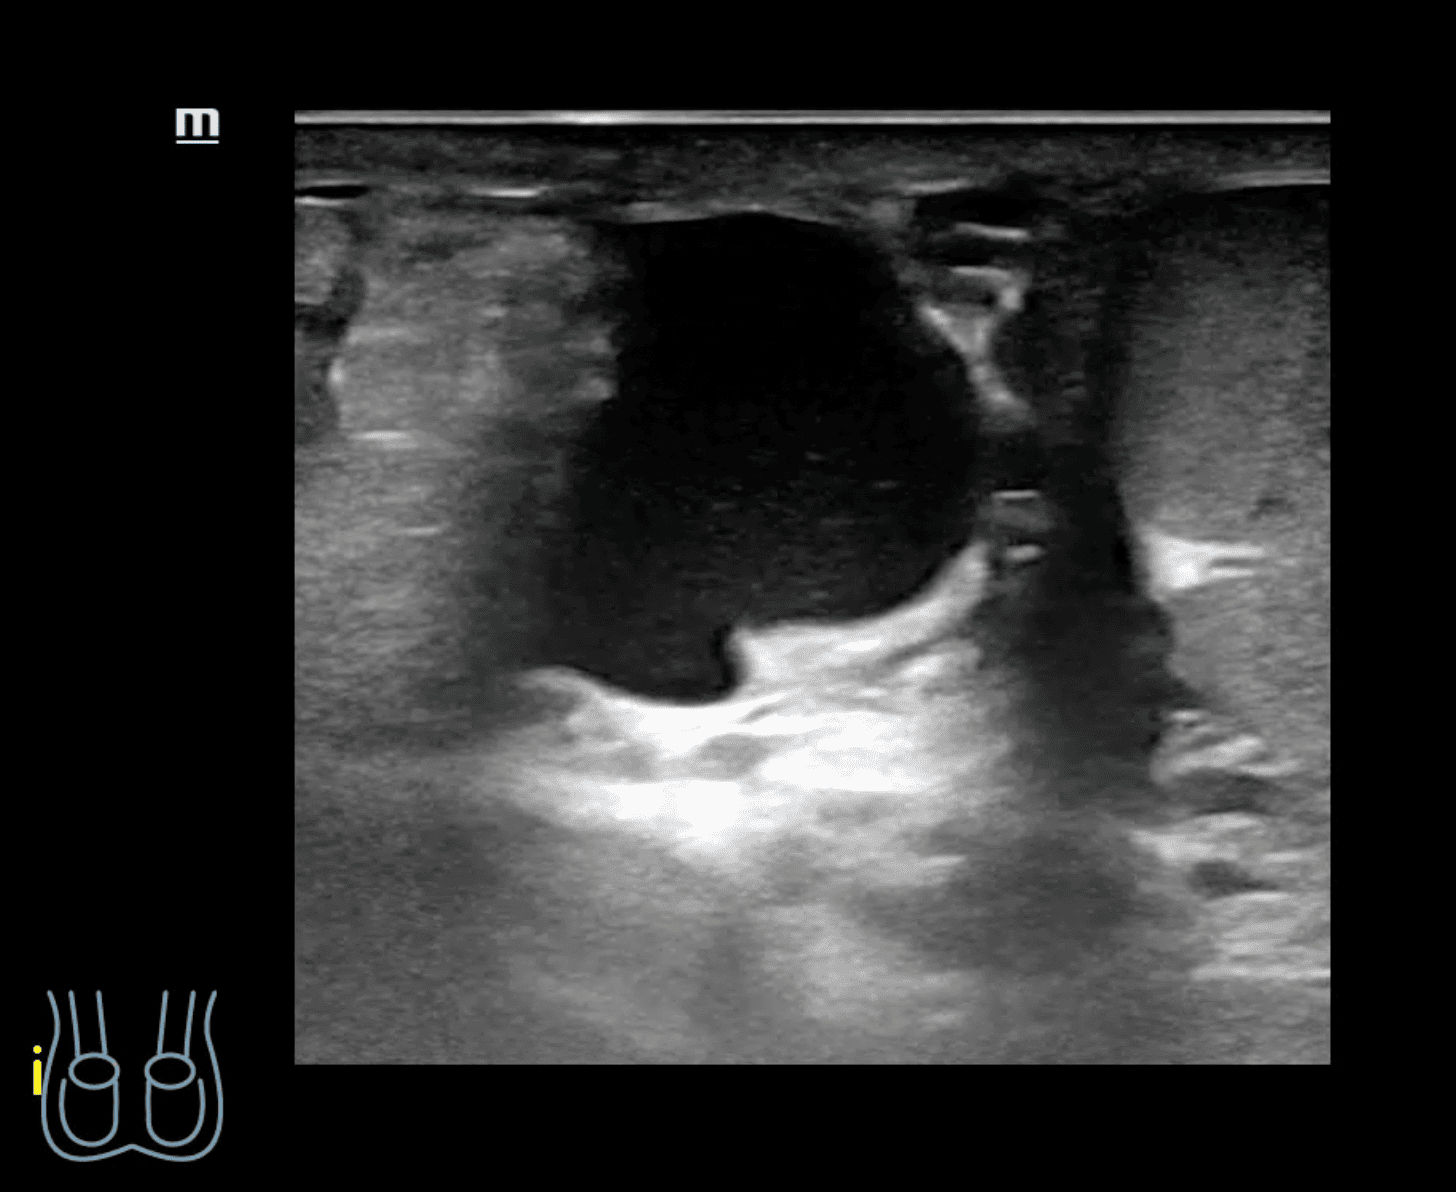

A nivel de escroto derecho, se observa imagen heterogénea con contenido intestinal compatible con hernia inguino-escrotal derecha. Testículos de aspecto normal.